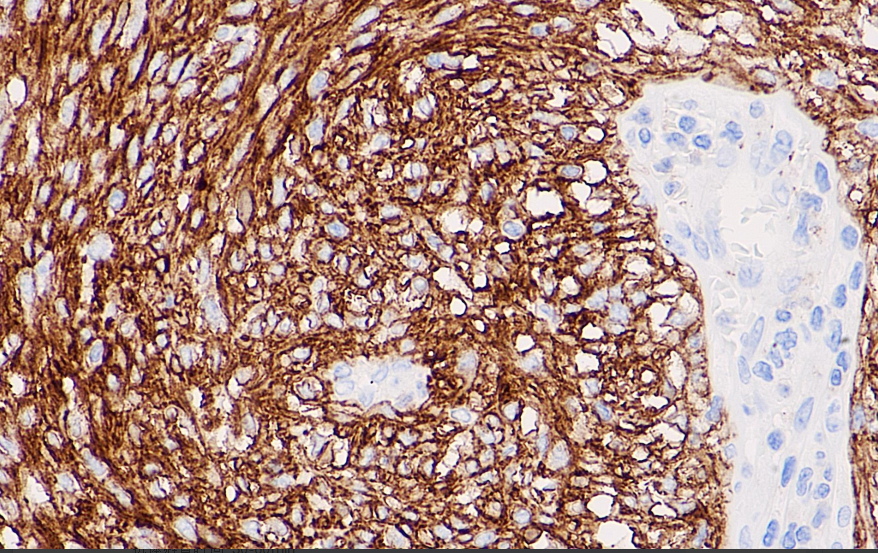

Positive control: Gastrointestinal mesenchymal tumor

The Dog1 gene is located on chromosome 11q13.Preliminary studies have confirmed that Dog1 protein is selectively expressed in gastrointestinal mesenchymal tumors and is a more sensitive and specific marker for GIST compared to KIT/CD117, both for gastrointestinal mesenchymal tumors with mutations in the KIT gene and the PDGFRA gene.

DOG1 antibody reagents can specifically bind to DOG1 molecular antigens. Immunohistochemistry kits containing DOG1 antibody reagents are suitable for the precise diagnosis of gastrointestinal stromal tumors.